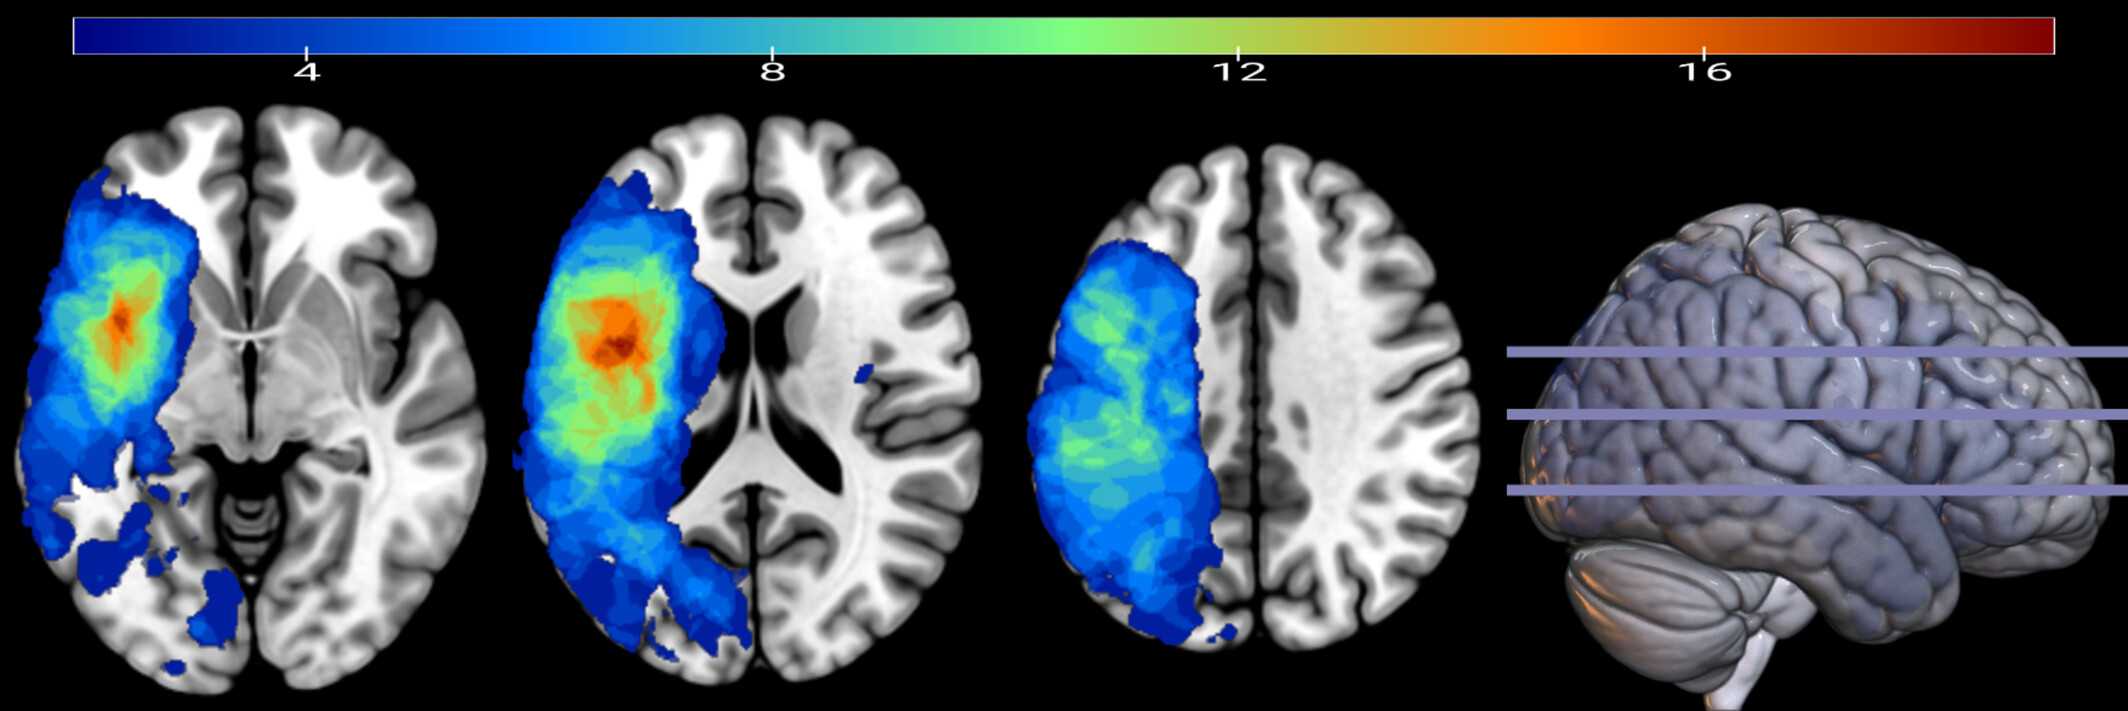

В исследовании участвовали 39 человек с афазией в хронической стадии инсульта и 24 здоровых участника, сопоставимых по возрасту. Все они слушали запись в течение 25 минут, а при обработке результатов учитывались способ произнесения, звонкость, округлость и локализация согласных и гласных звуков.

Сравнение динамики распознавания речи между двумя группами показало, что у людей с афазией фонетические признаки обрабатываются в мозге в течение более короткого времени, чем у контрольной группы. Предполагается, что при афазии трудности в анализе информации связаны не с тем, что речь не анализируется совсем, а с тем, что на обработку сигнала тратится меньше времени, и в результате не происходит полного распознавания всех фонетических признаков. То есть человек с афазией хуже обрабатывает речь, потому что мозг обрабатывает сигнал за меньший промежуток времени, чем у здорового человека.